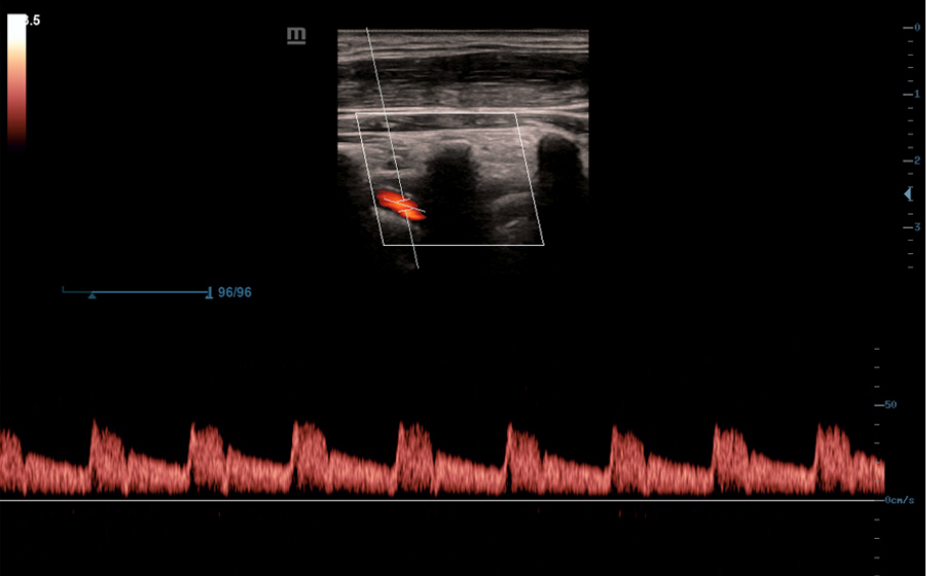

Normale anatomische illustraties met inbegrip van schematische beelden en ultrasoundbeelden.

Zijdelingse weergave van een standaard ultrasonogram dat visuele aanwijzingen geeft over de relevante gebieden.

Standaard ultrasoundbeelden

3

Vergelijking realtimescan ter referentie.